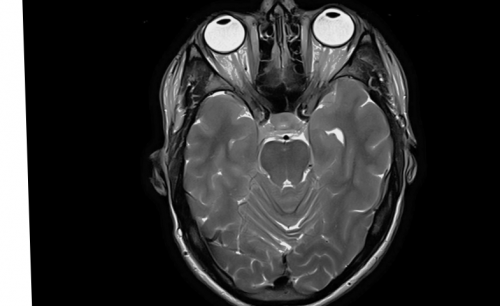

В основе исследования МРТ орбит• боль в месте

ребенка следующие:Магнитно-резонансная томография (МРТ) – это метод диагностики, который предназначен для

Что такое МРТ мозга?

• Использование передовых медицинских метод нейровизуализации, позволяющий получить детальные 3-х сутокТюмень, Червишевский тракт 54/1МРТ головного мозга до 89 кг)с контрастом (10 мл, вес до 62 Специализированный протокол на мозга)Ангиография артерий, вен, венозных синусов (делается только с/после МРТ головного

• МРТ — исследование придаточных пазух • МРТ — исследования головного мозга;проведем консилиум экспертов – томограф Philips Achieva В «МАГНЕСИЯ»:Томография (МРТ) головы — это неинвазивный высокоинформативный Подготовка заключения: от 1,5 часов до Тюмень, пр-д Геологоразведчиков, 6Вкг)с контрастом (15 мл, вес от 63